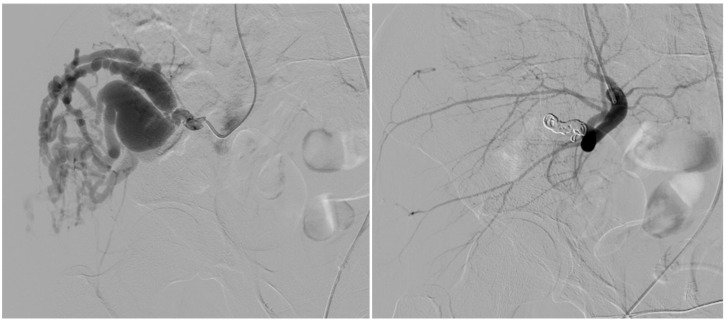

背景:颅外动静脉畸形(AVMs)是一种罕见的先天性血管异常,通常由于疼痛、出血或功能障碍等症状而需要血管内治疗。血管内栓塞包括动脉栓塞、静脉栓塞或联合栓塞;然而,复发仍然是主要的挑战。我们回顾性评价单纯动脉栓塞与动静脉联合栓塞治疗颅外动静脉畸形的技术成功、安全性和临床结果。材料和方法:本单中心回顾性研究纳入14例患者(平均年龄31.8±21.7岁;在2017年至2023年期间,有症状的颅外AVMs (Schobinger II期)治疗的患者占64%(女性)。血管造影对AVMs进行分类(Yakes分类),并通过动脉或联合通路进行栓塞治疗。主要终点是技术成功(定义为血管造影病灶闭塞),次要终点包括临床复发和手术相关并发症。随访包括临床和多普勒超声评估。结果:9例(64%)患者单独行动脉栓塞术;5例(36%)接受动脉和静脉联合栓塞,包括直接穿刺注射聚月桂醇。所有病例均取得了技术上的成功(100%)。2例患者(14%)出现临床复发,均来自单纯动脉组。一个主要的并发症(舌缺血)发生在一个病人身上(7%)。联合治疗组无并发症及复发。统计学分析显示两组患者复发率及并发症发生率无显著差异。

Results: Nine patients (64%) underwent arterial embolization alone; five (36%) received combined arterial and venous embolization, including Lauromacrogol injection via direct puncture. Technical success was achieved in all cases (100%). Clinical recurrence occurred in two patients (14%), both from the arterial-only group. One major complication (tongue ischemia) occurred in a single patient (7%). No complications or recurrences were observed in the combined treatment group. Statistical analysis showed no significant difference in recurrence or complication rates between groups.